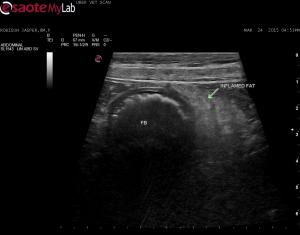

Fluid absorbing FB so not big

Fluid absorbing FB so not big dilation evident prior to the fb. The second video has perserosal fat inflammation so makes it an emergency.

FB confirmed at surgery.  I

FB confirmed at surgery.  I have added the photos before and after – mouse toy.